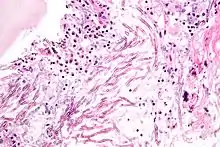

Cryptococcus neoformans can cause a severe form of meningitis and meningo-encephalitis in patients with HIV infection and AIDS. The majority of Cryptococcus species live in the soil and do not cause disease in humans. Cryptococcus neoformans is the major human and animal pathogen. Papiliotrema laurentii and Naganishia albida, both formerly referred to Cryptococcus, have been known to occasionally cause moderate-to-severe disease in human patients with compromised immunity. Cryptococcus gattii is endemic to tropical parts of the continent of Africa and Australia and can cause disease in non-immunocompromised people.[1]

Infecting C. neoformans cells are usually phagocytosed by alveolar macrophages in the lung.[11] The invading C. neoformans cells may be killed by the release of oxidative and nitrosative molecules by these macrophages.[12] However some C. neoformans cells may survive within the macrophages.[11] The ability of the pathogen to survive within the macrophages probably determines latency of the disease, dissemination and resistance to antifungal agents. In order to survive in the hostile intracellular environment of the macrophage, one of the responses of C. neoformans is to upregulate genes employed in responses to oxidative stress.[11]